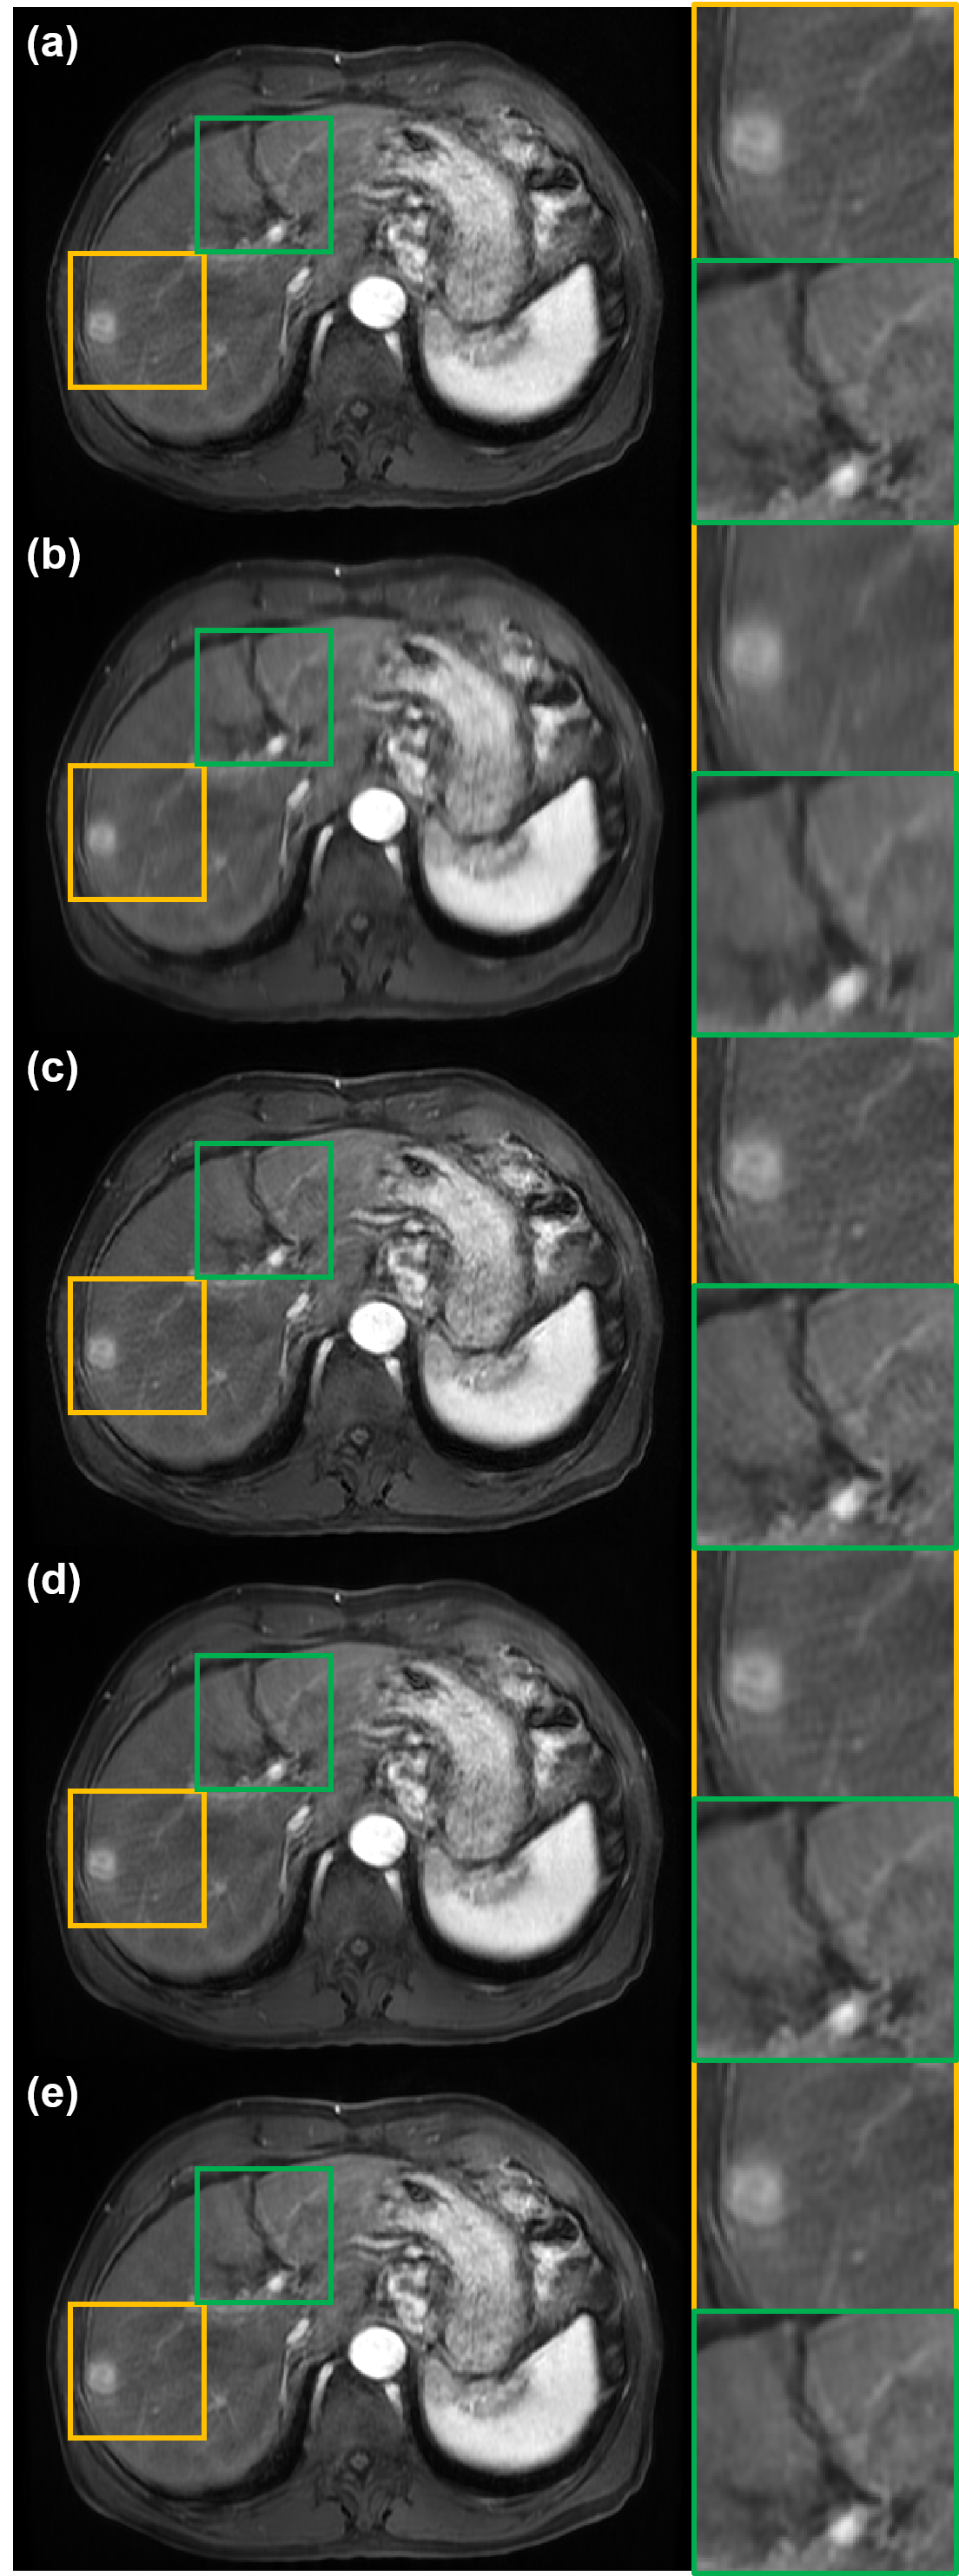

Because the simulated motion artifacts only consider rigid motion artifacts, it should be verified that the method can also be applied to non-rigid in vivo motion artifact removal. In Fig. 5(a), motion artifacts due to transient dyspnea degrade the quality of liver MR image. We attempt to remove motion artifacts in Fig. 5(a), and results are shown in Fig. 5(b) to (e). Again, MARC removes not only motion artifacts but also detailed structures of blood vessels, so the reconstructed image is extremely blurry (Fig. 5(b)). Conversely, in Fig. 5(c), Cycle-MedGAN V2.0 makes the image sharper, but it also amplifies motion artifacts or noise in the input image. Next, the bootstrap subsampling and aggregation method also fails to remove the motion artifacts. Specifically, as shown in the yellow and green boxes of Fig. 5(d), motion artifacts around the blood vessels remain in the output image. Unlike comparison methods, the proposed method successfully removes the motion artifacts and reduces the noise level of the input image. Furthermore, our method reconstructs detailed structures. For example, in the yellow box of Fig. 5(e), the sharpness of the lesion increased as the motion artifact disappeared. Also, the vascular structure is recovered due to the reduction of motion artifacts as shown in the green box of Fig. 5(e). Through the experiment using in vivo motion-corrupted data, we confirmed that the proposed method also removes in vivo motion artifacts that contain the non-rigid motion of patients.